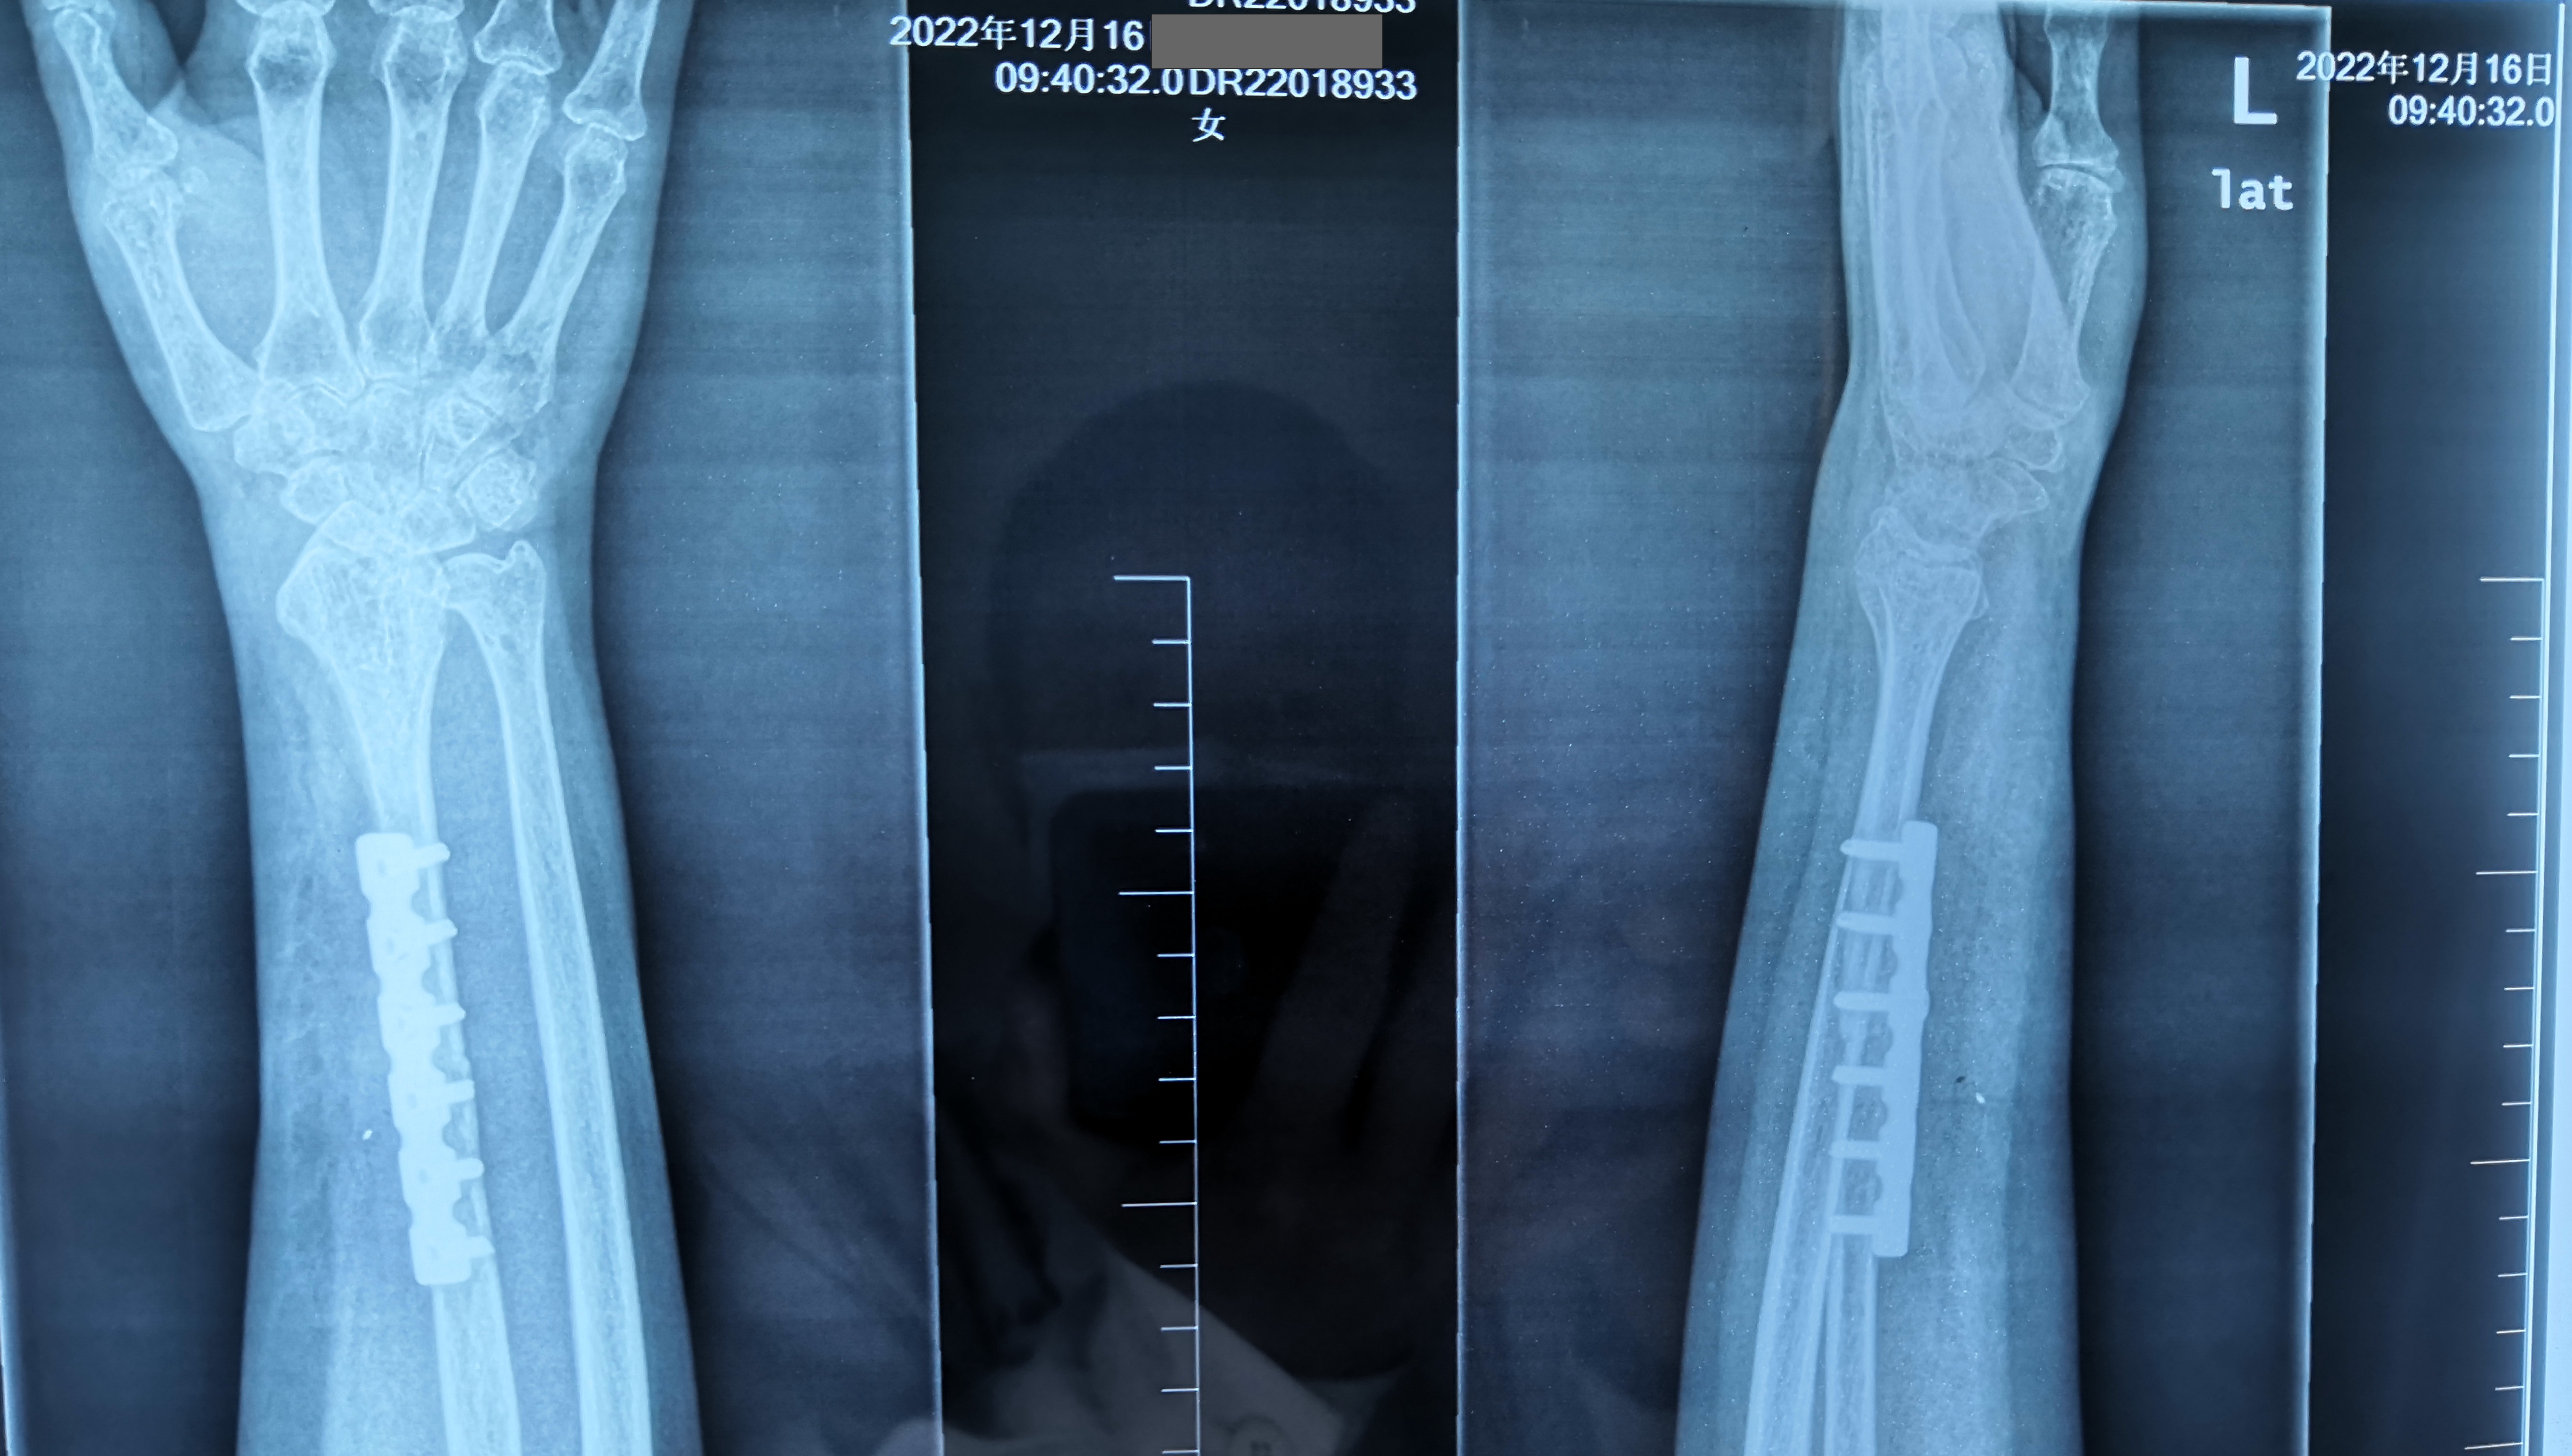

官常和醫(yī)生和他的顯微外科手術(shù)團(tuán)隊(duì)經(jīng)過充分的術(shù)前準(zhǔn)備后,成功為患者順利的進(jìn)行了左側(cè)橈骨下段瘤段切除加游離對(duì)側(cè)帶血管蒂腓骨移植重建腕關(guān)節(jié)術(shù)。

術(shù)后3個(gè)月,患者手術(shù)的小腿、前臂功能逐漸恢復(fù),影像檢查一切正常,手術(shù)成功?;颊吆图覍偬氐厮蛠礤\旗表示感謝。